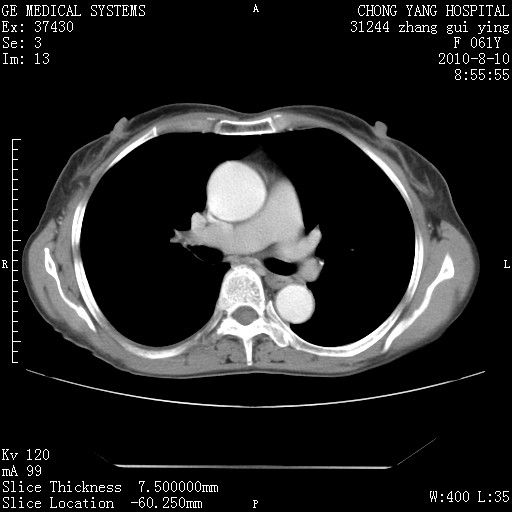

标题: CT28314:F61Y胸部增强,发热咳嗽一周入院,后面的为一周前平

1、支持考虑右侧中央型肺癌伴右肺中叶节段性不张及下叶支气管黏液痰栓    2、左肺上叶舌段感染。

支持3楼意见,还要考虑:纵隔及肺门淋巴结转移、右侧少量胸腔积液。

确切的说:1:右肺下叶中心型肺癌侵及中叶支气管并中叶不张,纵膈淋巴结转移。2:左肺舌叶炎症。3:右侧胸腔少量积液

块影平扫32hu,动静脉期62-70hu.

考虑右下肺肺癌,纵隔淋巴结转移i。